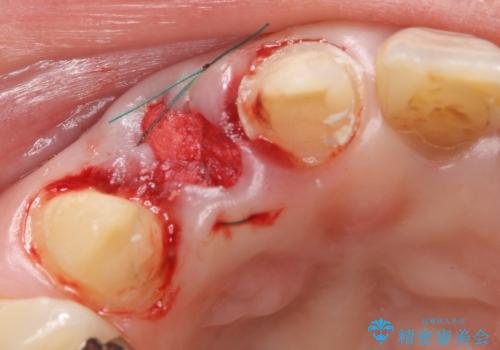

診査の結果右上2は歯根が破折しており、それが原因で骨及び歯肉の吸収が起きていました。

このまま右上2の抜歯を行うとさらに歯茎が下がる恐れがあったため、歯の挺出によって骨レベルを回復した上で抜歯し、歯槽堤保存術(抜歯窩に人工骨を填入する手術)を行いました。